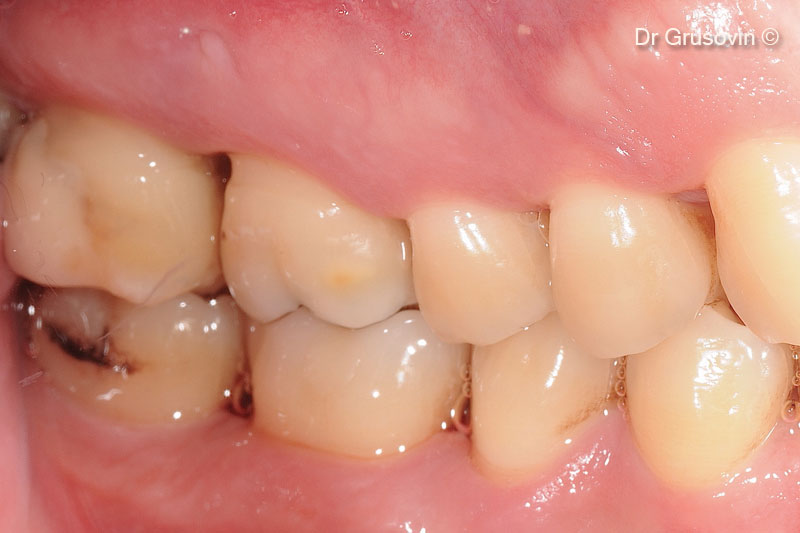

1. Healthy patient, non smoker intraoral clinical view buccal

2. #16 vital, furcation III involvement vestibular distal